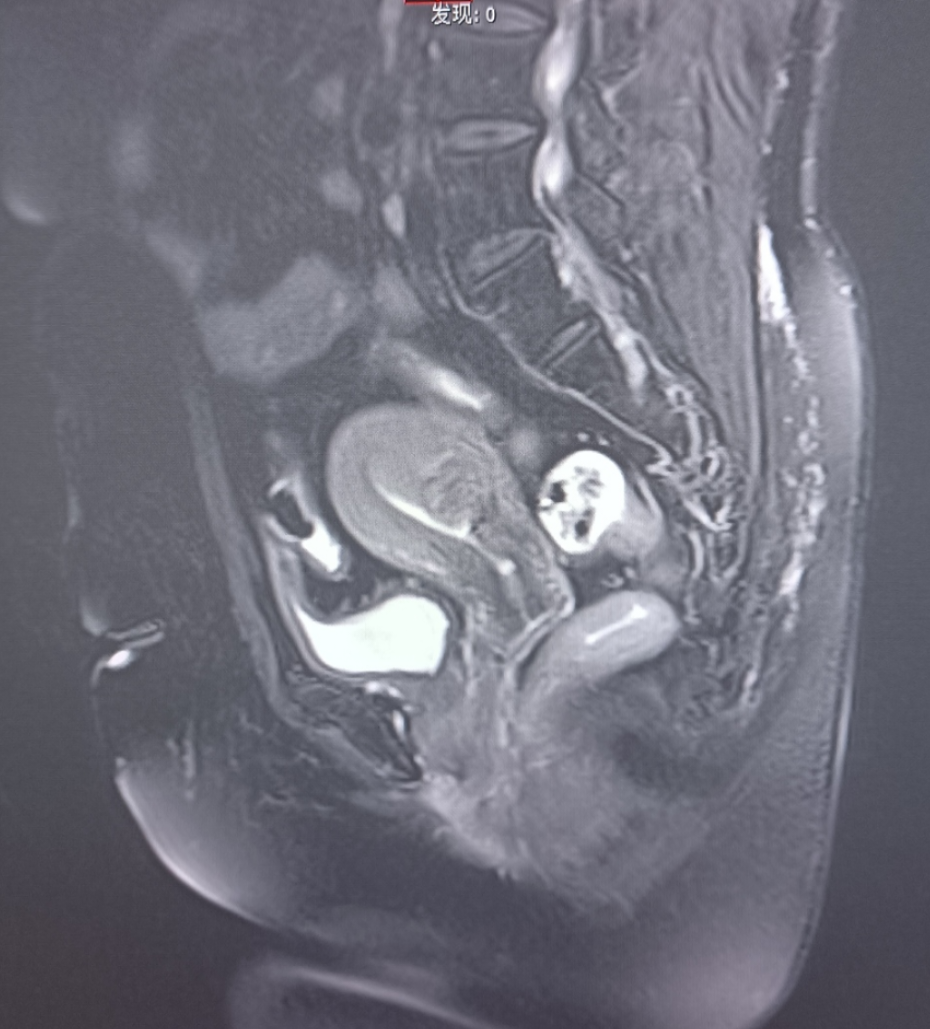

患者57岁,体重75千克,身高157厘米,血压147/100mmHg,绝经3年,阴道流血水样分泌物3个月,淋漓不尽,自服抗生素治疗无效就医。当地医院行妇科彩超检查发现子宫内膜厚约13毫米,宫内节育器位置正常,给予取环+诊断性刮宫,术后病理组织学检查报告提示:低分化癌,建议免疫组化标记明确类型。随就诊我院。

MRI:

术前诊断:子宫内膜癌(低分化)

术后诊断:子宫内膜样低分化腺癌(IIIC1)(微卫星稳定型)